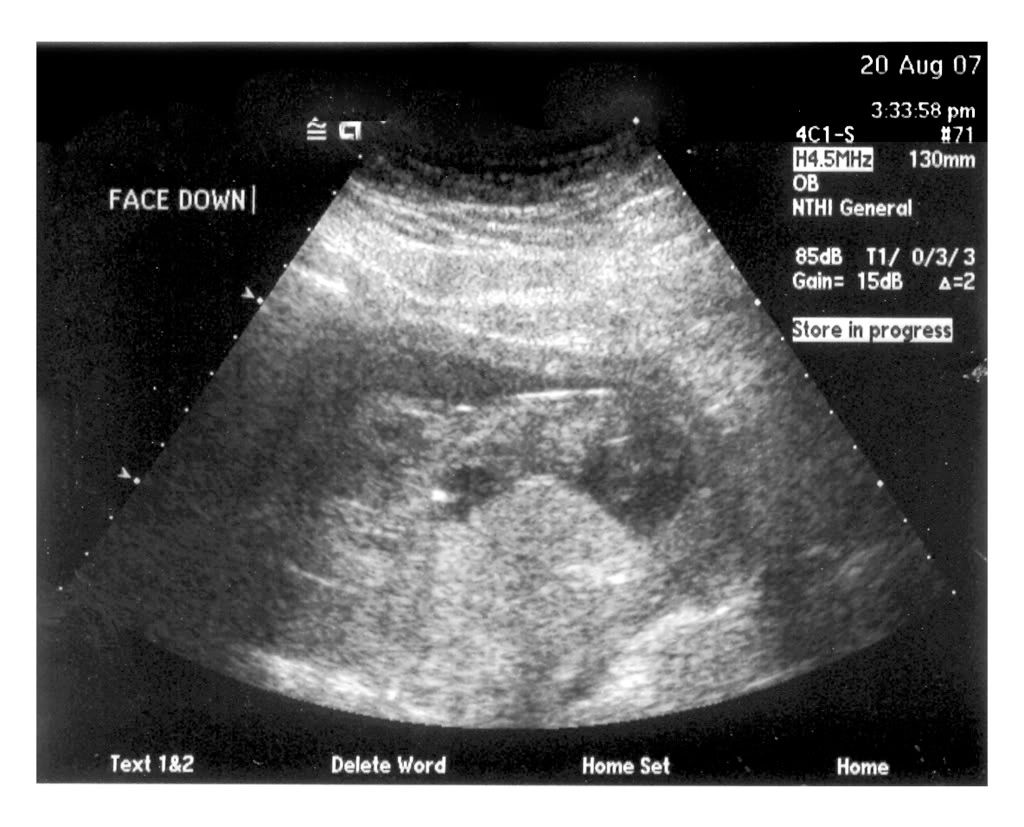

I had my NT test yesterday (8-20) and Chuck and I were able to see and hear the baby. It was a very cool experience to see what actually looked like a baby this time. It was dancing around, waving it's arms and kicking, though it wouldn't cooperate and turn over for the tech. It's hard to see on the picture, but we have a great profile view. The head is on the left, the butt on the right, and it's face down. Click on the photo to see larger image (1024x768).

The heartbeat was 153 beats per minute.